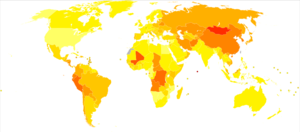

يشاهد سرطان المعدة غالباً في الأعمار المتقدمة، وتختلف نسب الإصابة به بحسب الجنس، إذ تبلغ الإصابة عند الذكور ضعف إصابة الإناث. كما تختلف نسب الإصابة والوفيات بسببه حسب التوضع الجغرافي، فتشاهد نسب عالية منها في بلدان معينة مثل تشيلي وكوستاريكا وهنغاريا والبرتغال وسنغافورة ورومانيا (الشكل ـ1). وتحدث أعلى نسب الوفيات بسببه في اليابان (50% عند الذكور، و40% عند الإناث). ويُعتقد أن السبب الرئيس لارتفاع نسب الإصابة في تلك البلاد عائد إلى مسرطنات بيئية environmental carcinogens، مصدرها الغذاء غالباً.